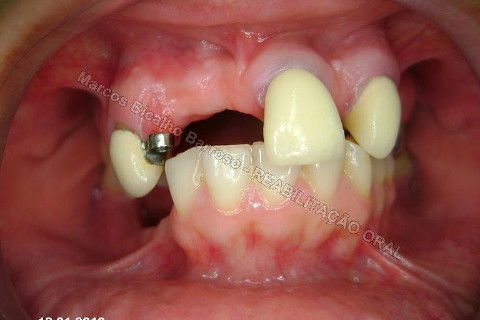

Paciente sexo feminino, 40 anos, queixava-se da situação da PPR superior, sem estabilidade, fraturas constantes nos dentes instalados. Sua vontade era resolver somente o problema da arcada superior, por questões financeiras. Logo no exame clínico inicial verifiquei a necessidade da reabiltiação inferior, pois este caso consistia em desarmonia oclusal severa, principalmente pela extrusão dos elementos 13,14 e 15 devido ausência de várias unidades inferiores. A proposta aceita pela paciente foi a instalação de 5 implantes na mandíbula + 5 implantes na maxila + tratamento endodôntico, osteoplastia e gengivoplastia nos dentes extruídos, incluindo núcleos metálicos e coroas em metalocerâmica (13,14,15). As coroas sobre implantes serão incialmente provisórias em resina fotopolimerizável e posteriormente metalocerâmica, de acordo com as possibilidades da paciente. Os procedimentos nos elementos extruídos serão apresentados em momento oportuno.